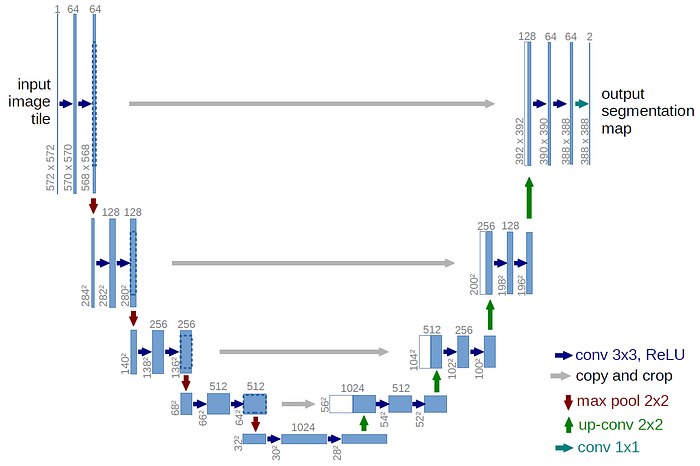

尽管 U-Net 专注于生物医学图像,但其灵活的架构允许它有效地用于其他类型的图像数据。

U-Net 的命名是因为它的结构类似于字母 U,如图所示。我们在输出端得到分割后的输入图像。U-Net 的架构是独特的,因为它由收缩路径和扩展路径组成。

收缩路径(编码器)从输入图像中提取属性图,而扩展路径(解码器)将这些属性转换回更高分辨率的形式。跳跃连接允许低级和高级属性结合,从而实现更好的分割性能。